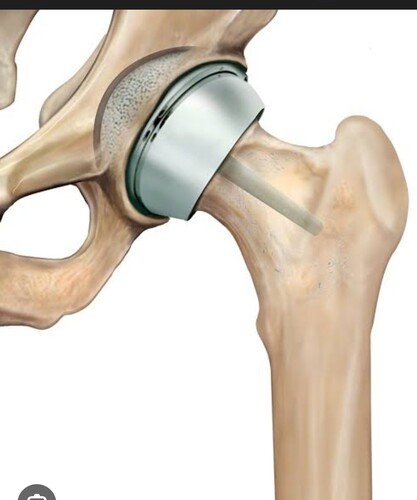

Prótese de fêmur para Marlucio Benevides

Sou esposa de Marlucio, criei essa vakinha para arrecadar uma contribuicao beneficiente para a compra de uma protese de fêmur para Marlucio Benevides Das Neves, ele foi diagnosticado com astrose a 2 anos,agradeço a ajuda de todos! ver tudo

Sou esposa de Marlucio, criei essa vakinha para arrecadar uma contribuicao beneficiente para a compra de uma protese de fêmur para Marlucio Benevides Das Neves, ele foi diagnosticado com astrose a 2 anos,agradeço a ajuda de todos!